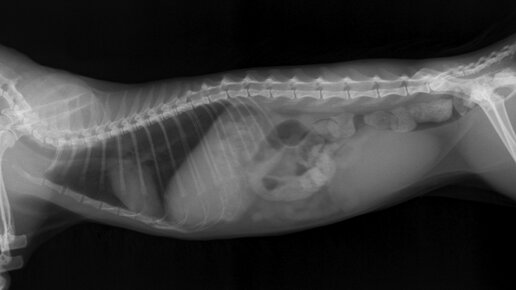

Это был мейн-кун. Девочка. Стерилизована. 5 лет. Поступила она в клинику с копростазом. Это болезнь, которая возникает после затяжного запора. Простыми словами - каловые массы стоят в прямой кишке и не хотят выходить. Чаще всего это заболевание возникает из-за неврологического заболевания, нарушениях в работе пищеварительной системы или из-за опухоли. В нашем случае, болезнь возникла из-за того, что что-то пошло не так в работе кишечника после того, как кошка сбежала из дома и где-то гуляла около недели...